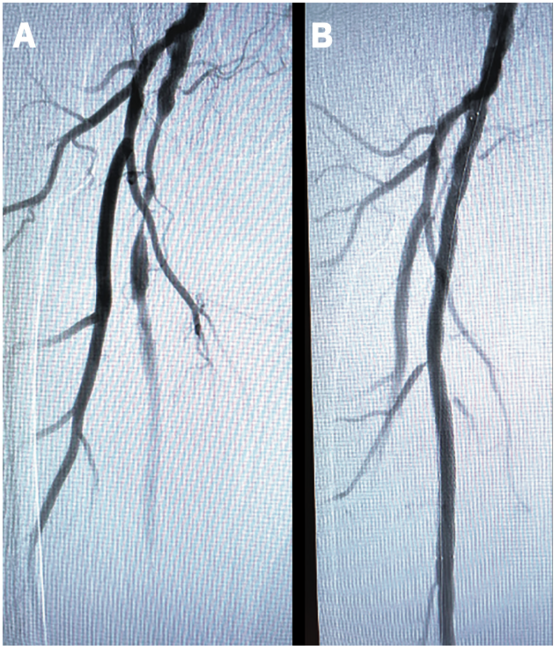

Given the shortage of time slots due to staffing issues during the COVID pandemic, we elected to proceed with the right lower extremity angiography instead of finding another peripheral cath lab schedule opening. A 5 Fr pigtail was advanced to the distal aorta and angiography demonstrated a 95% proximal SFA stenosis (Figure 1A). We decided to exchange the 5 Fr radial sheath with a 6 Fr, 119 cm R2P DESTINATION SLENDER, advanced over an .035-inch GLIDEWIRE ADVANTAGE® to the right common femoral artery. An .018-inch GLIDEWIRE ADVANTAGE TRACK™ Guidewire (Terumo) was successfully advanced across the lesion and a 6 mm x 120 mm R2P METACROSS Balloon was used to predilate the lesion. A 7 mm x 150 mm R2P MISAGO RX Self-Expanding Peripheral Stent was advanced over the wire and deployed at the lesion. Post dilation was performed with the same balloon.

Post-intervention angiography revealed excellent results with no residual stenosis and brisk distal flow through the SFA (Figure 1B). The sheath was removed and a TR Band® (Terumo) was applied. The patient tolerated the procedure extremely well. The total added time was about 10 minutes and the patient was able to be discharged home in two hours. Radial access allowed us the flexibility of using the same access site for angiography of both the coronary and peripheral arteries, as well as peripheral intervention. The use of radial access also permitted rapid, safe discharge with a low risk of bleeding and complications.